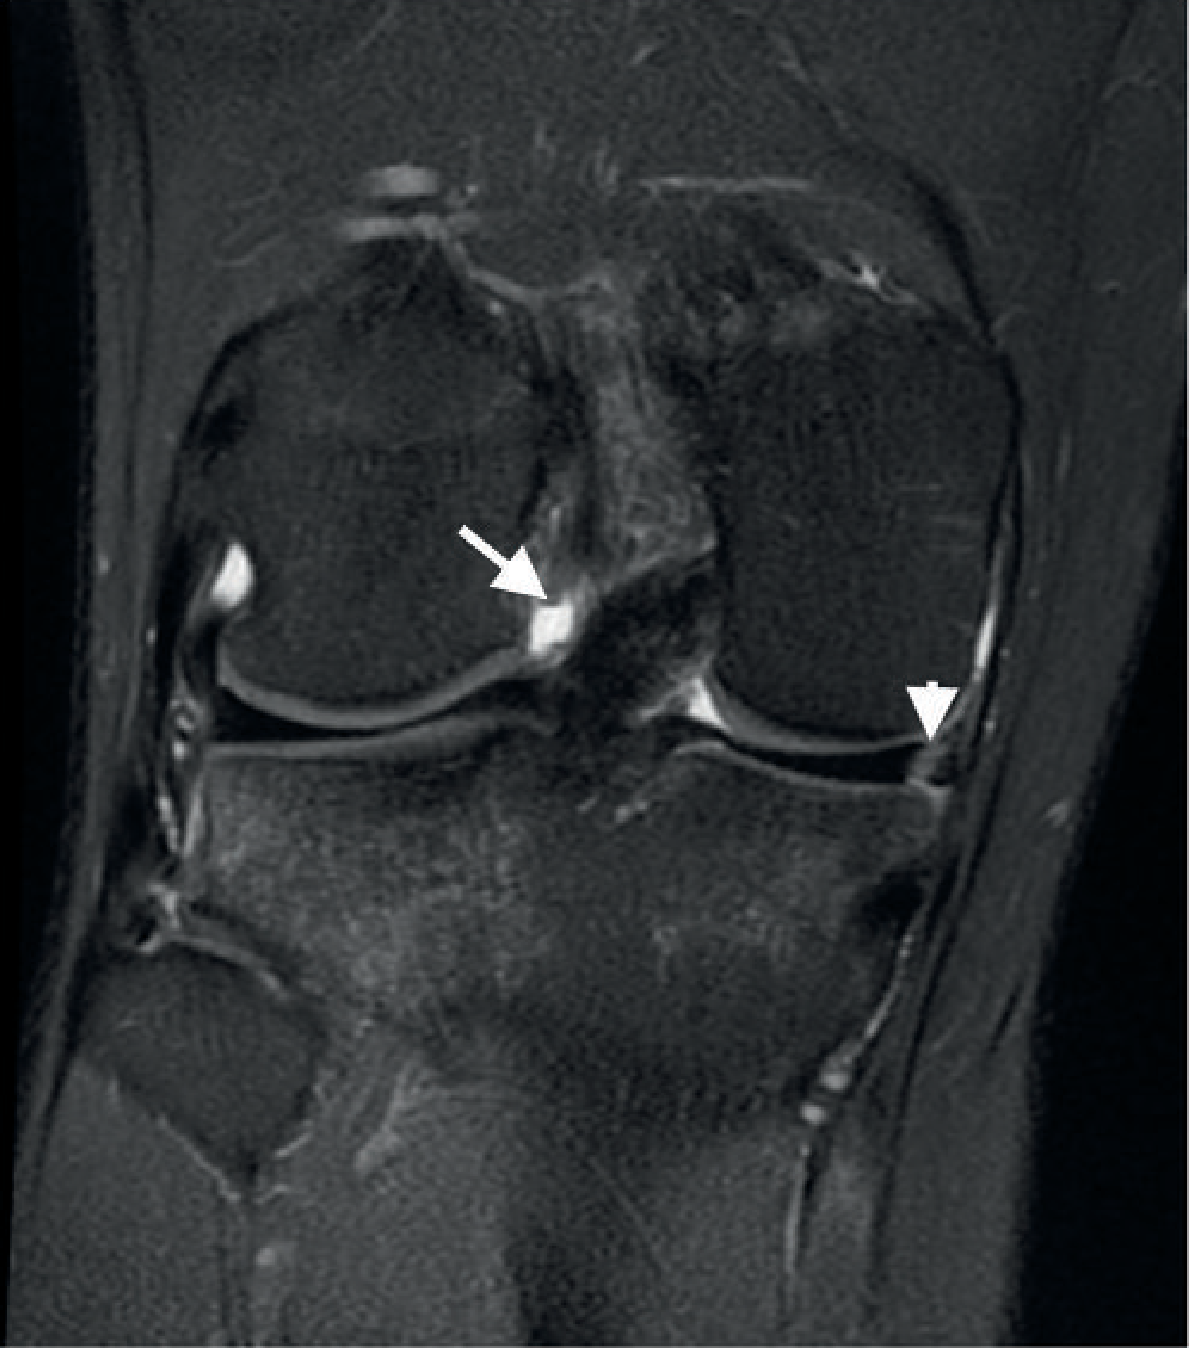

Coronal MRI showing medial meniscus tear

Coronal MRI of the knee showing a medial meniscus tear (Gray's Anatomy for Students)

Coronal PD fat-saturated MRI — vertical cleft in the peripheral body of the medial meniscus (arrowhead); note also ACL rupture (arrow)

Longitudinal tear — peripheral medial meniscus (Grainger & Allison's Diagnostic Radiology)